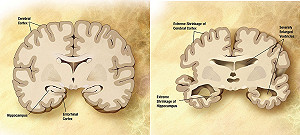

1滴血30分內 輕鬆檢測阿茲海默症